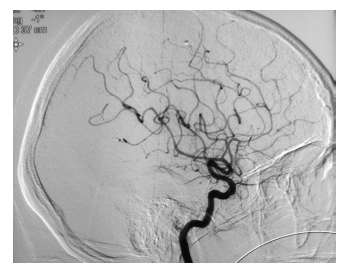

La infección por el virus de inmunodeficiencia humana (VIH) se ha asociado con una variedad de síntomas reumáticos, los cuales pueden coexistir con enfermedades reumáticas autoinmunitarias, tales como la artritis…